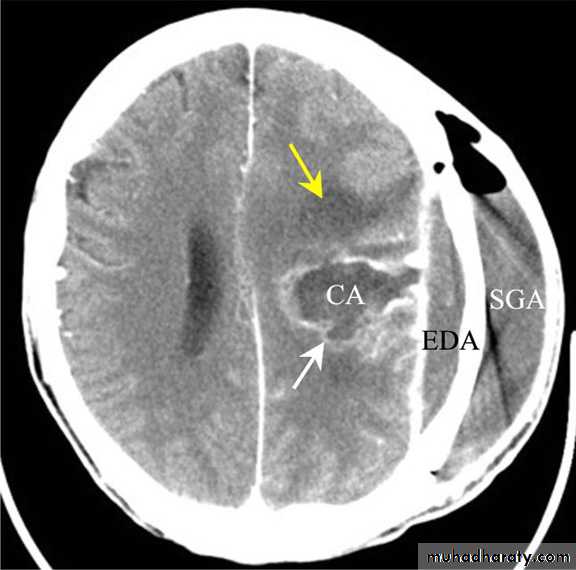

Subdural Empyemas

Neurosurgery

• CT scanning;

Despite subdural empyema is a neurosurgical emergency, diagnosis is often delayed as the collection on CT is usually so slight and frequently missed.

2. MRI : useful when the diagnosis is doubtful.